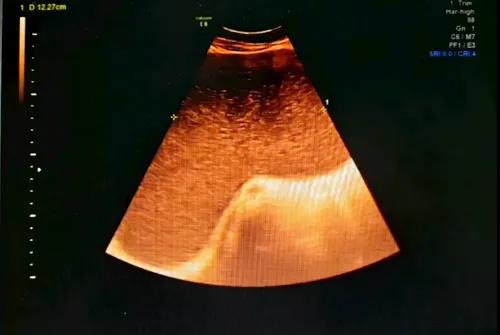

收住院后,经检查考虑患者为盆腹腔巨大肿瘤,妇科来源可能性大,经妇科二病房汤艳梅主任医师会诊后转入我院妇科二病房。邹忠文主任医师、汤艳梅主任医师团队进一步治疗,超声检查提示:盆腹腔肿物大小594*640*114mm上至剑突,下至盆腔,左右至侧腹腔液性暗区伴细密光点,边界清,轮廓规则。经过多学科(MDT)会诊和详细影像学评估,妇科二团队做出一个大胆而负责任的决定:迎难而上,采用腹腔镜微创技术为她切除肿瘤。